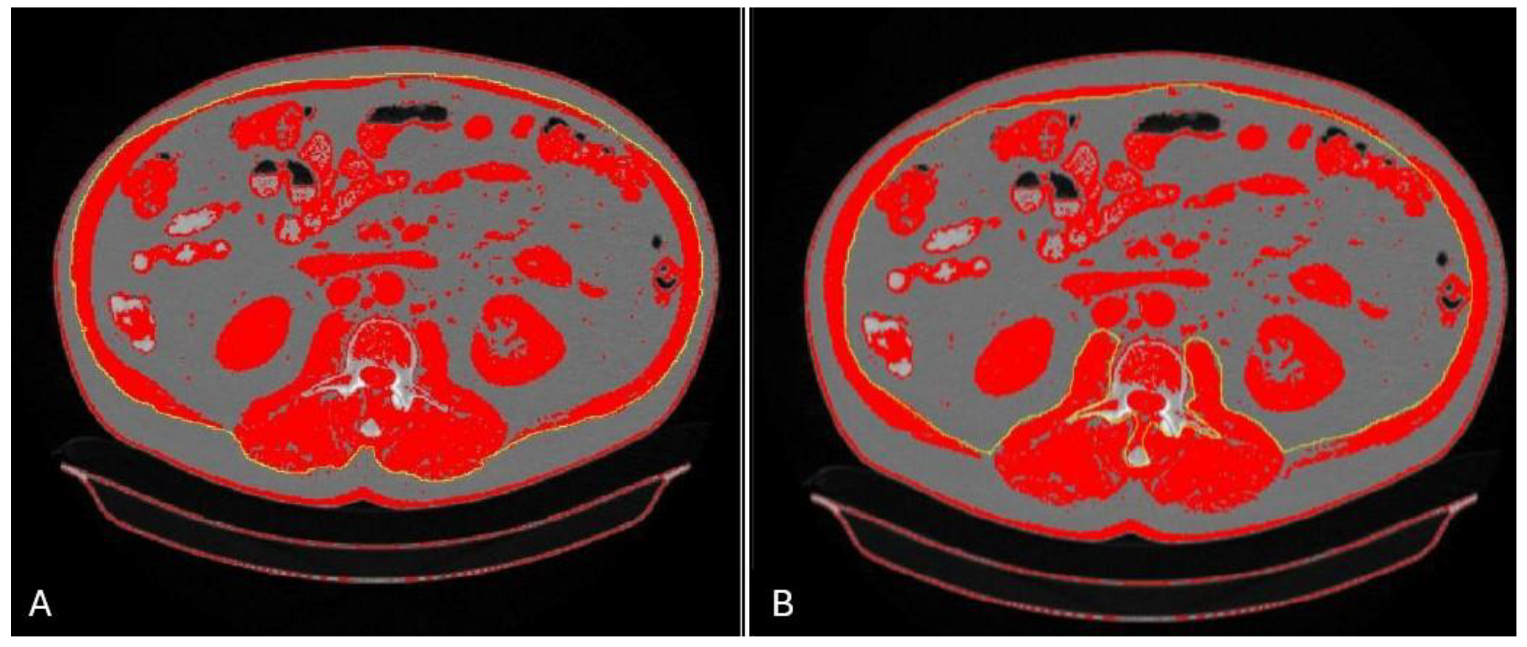

4.1. Multislice Computed Tomography: L3 SMI

- Polan, D.F.; Brady, S.L.; Kaufman, R.A. Tissue segmentation of computed tomography images using a Random Forest algorithm: A feasibility study. Phys. Med. Biol. 2016, 61, 6553–6569. [Google Scholar] [CrossRef] [PubMed]